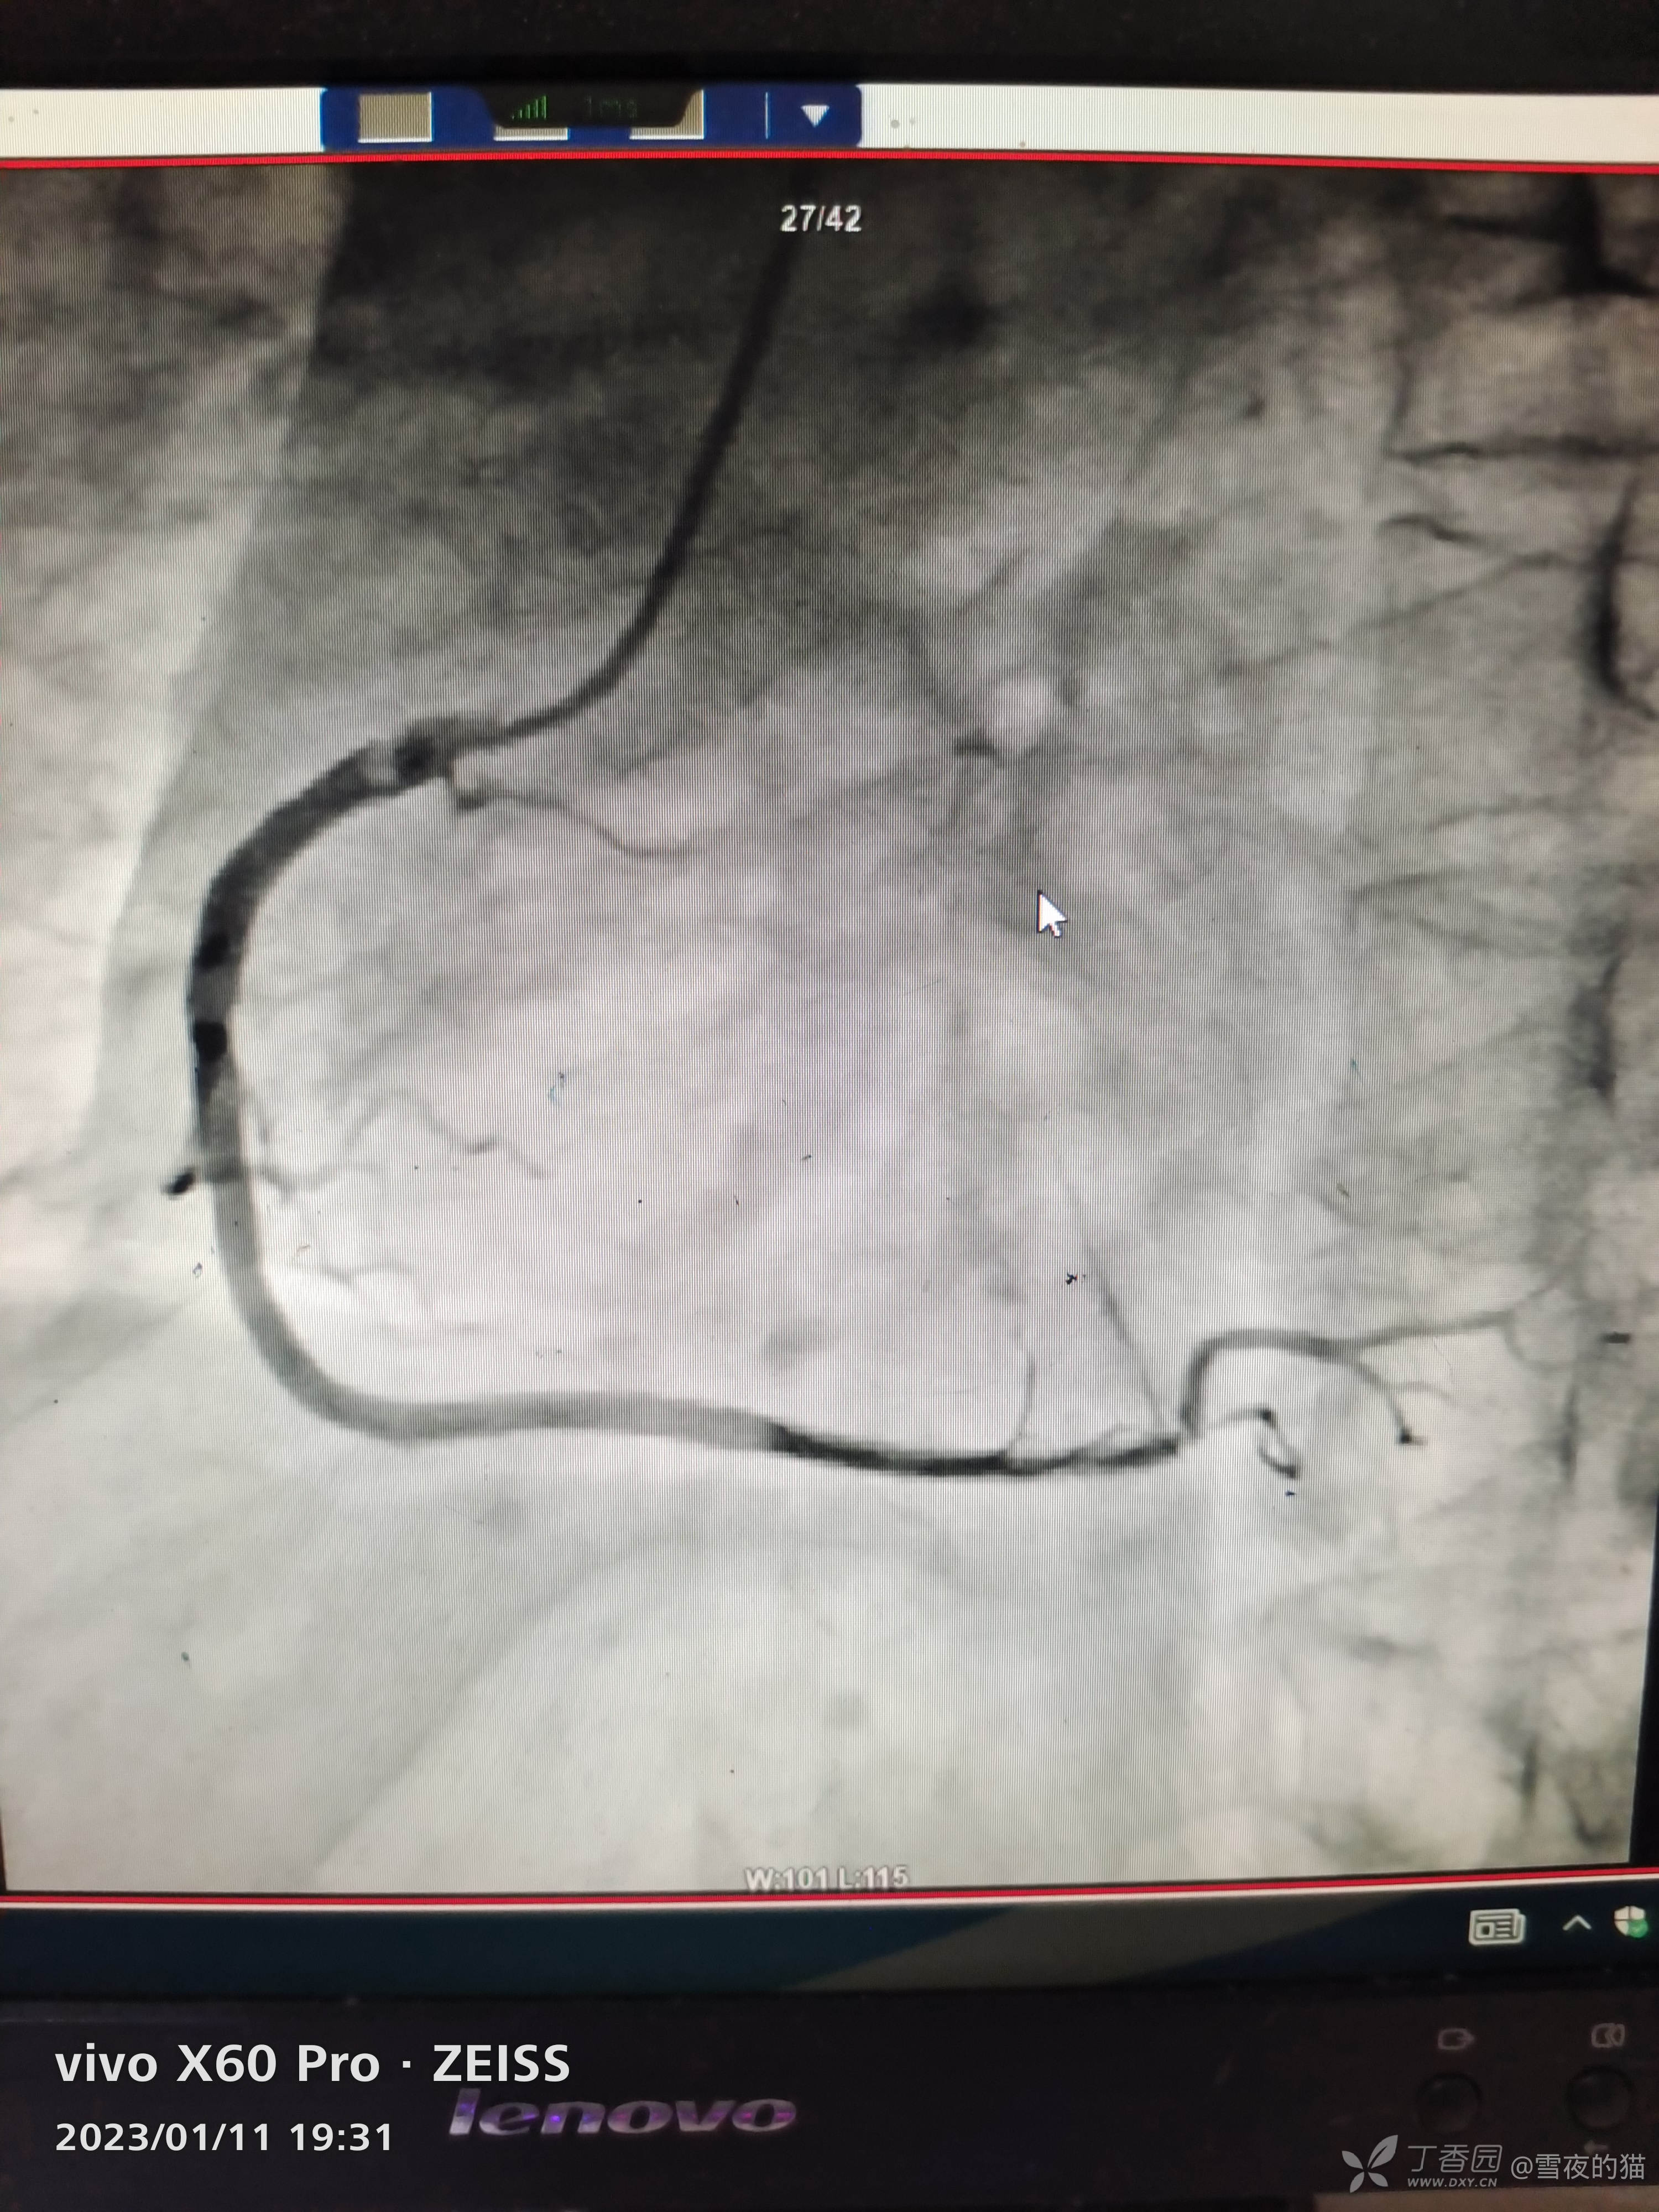

完善冠脉造影提示冠脉硬化,